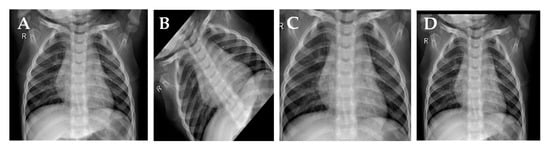

3.3. Visualization of the Activation Layer